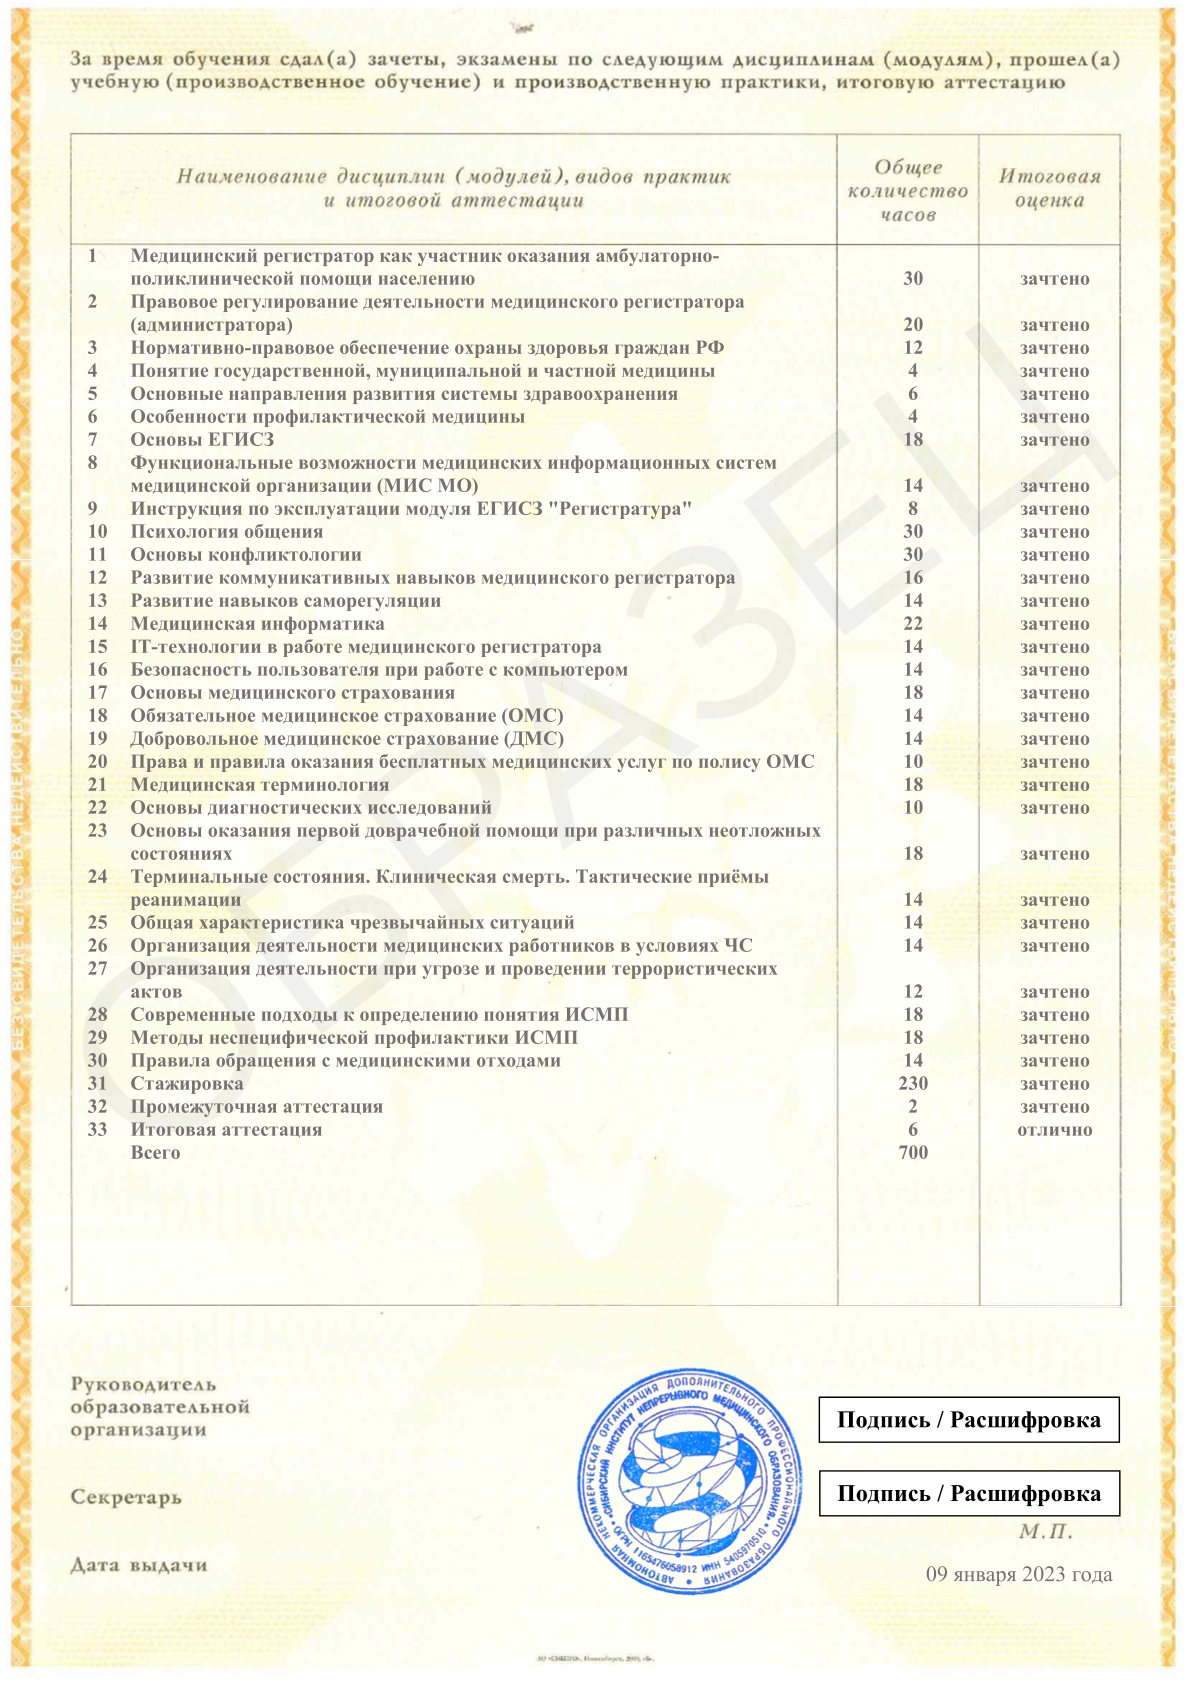

Смотреть документ

Смотреть документ